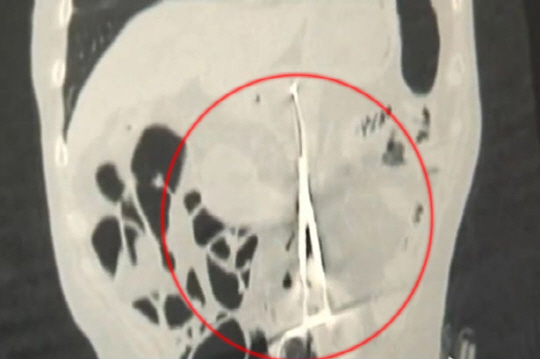

무려 12년 동안 뱃속에 의료용 가위가 있던 환자의 사연이 공개돼 충격을 주고 있다.

이후 그는 계속된 복통에도 "목숨을 건진 것만으로 위로가 된다"며 병원을 찾지 않았다. 하지만 최근 들어 체중이 급격히 감소하는데다 복통의 빈도가 잦아지자 병원을 찾게 됐다.

그를 진찰한 의료진은 "가위가 어떻게 뱃속에 남겨졌는지 도대체 이해가 안된다"며 "환자가 엄청난 고통을 겪었을 것"이라고 말했다. 이어 그는 "12년전 그를 수술했던 의사를 찾아봤지만 이미 세상을 떠나 이유를 알 수가 없었다"고 덧붙였다.